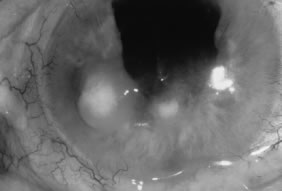

Candida infection typically produces epithelial ulceration, focal necrotizing stromal inflammation, moderate cellular infiltrate and edema in the adjacent stroma, and mild or moderate iritis in the early stages, indistinguishable from bacterial keratitis (Figs. 15, 16, and 17). Fungal elements cannot be detected by biomicroscopy. If untreated, the keratitis evolves to produce dense suppuration and necrosis of the deep stroma. Although multifocal suppuration may develop in polymicrobial keratitis, there is no distinctive sign of mixed Candida and bacterial infection (Fig. 18).

Advanced, severe filamentous fungal or yeast keratitis is indistinguishable from keratitis caused by virulent bacteria such as Staphylococcus aureus or Pseudomonas aeruginosa. The area of epithelial and stromal ulceration is large. Dense, opaque, homogenous, yellow-white stromal necrosis develop and is surrounded by confluent cellular infiltrate and full-thickness stromal edema (Figs. 19, 20, 21). Hyphal elements may penetrate Descemet's membrane and endothelium and be visualized in the anterior chamber. Fibrinous material accumulates over the endothelium, anterior chamber angle, and iris. Pain is typically severe. Secondary ocular hypertension may ensue. Progressive stromal necrosis leads to corneal perforation and, rarely, consecutive endophthalmitis.